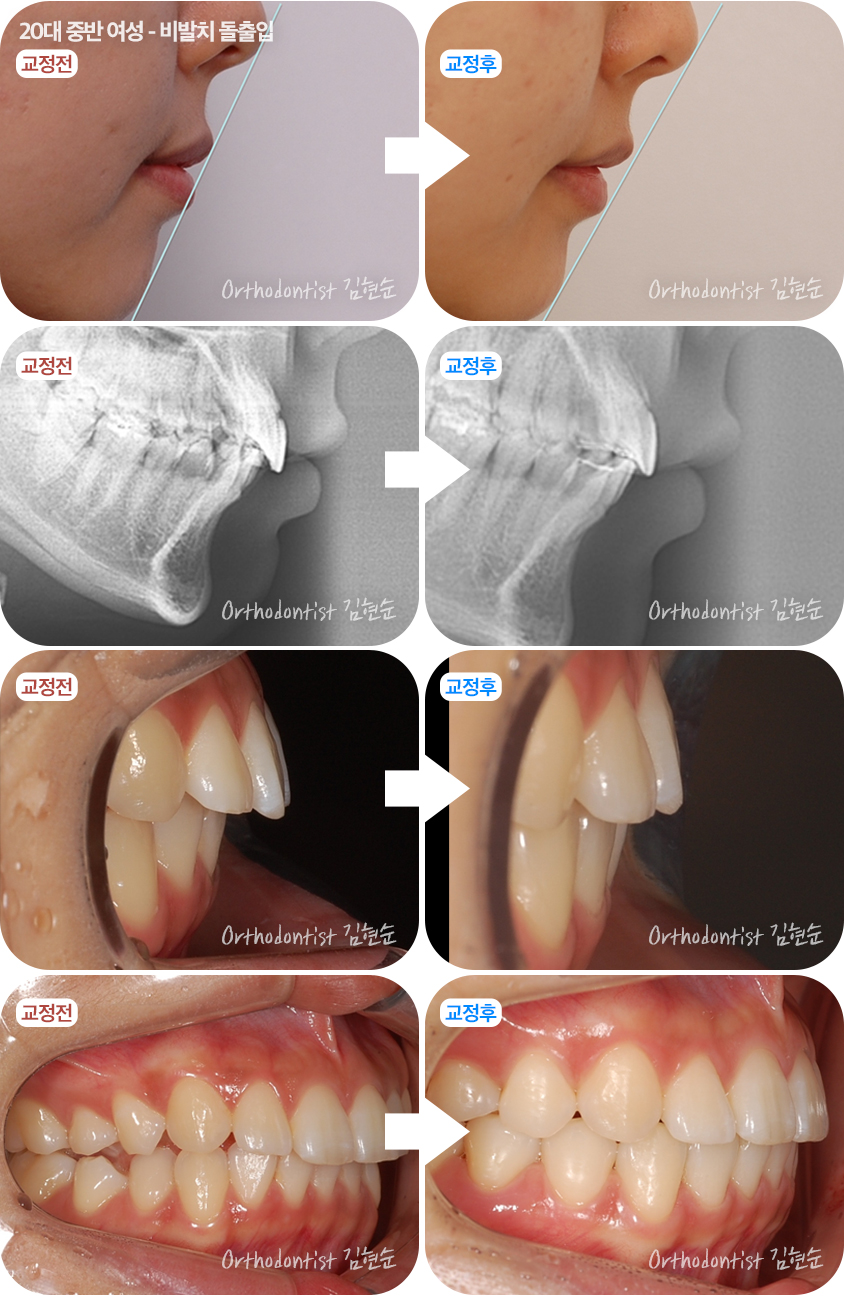

아래 사진은 20대 중반 여성분의 비발치로 돌출입을 개선한 사례입니다.

이처럼 잇몸뼈가 나와있지 않고 치아만 나와있고 덧니가 있어도 치아를 빼지않고 뒷 공간을 이용해서 돌출입을 개선할 수 있습니다.

전후 사진으로 비교를 해보시죠